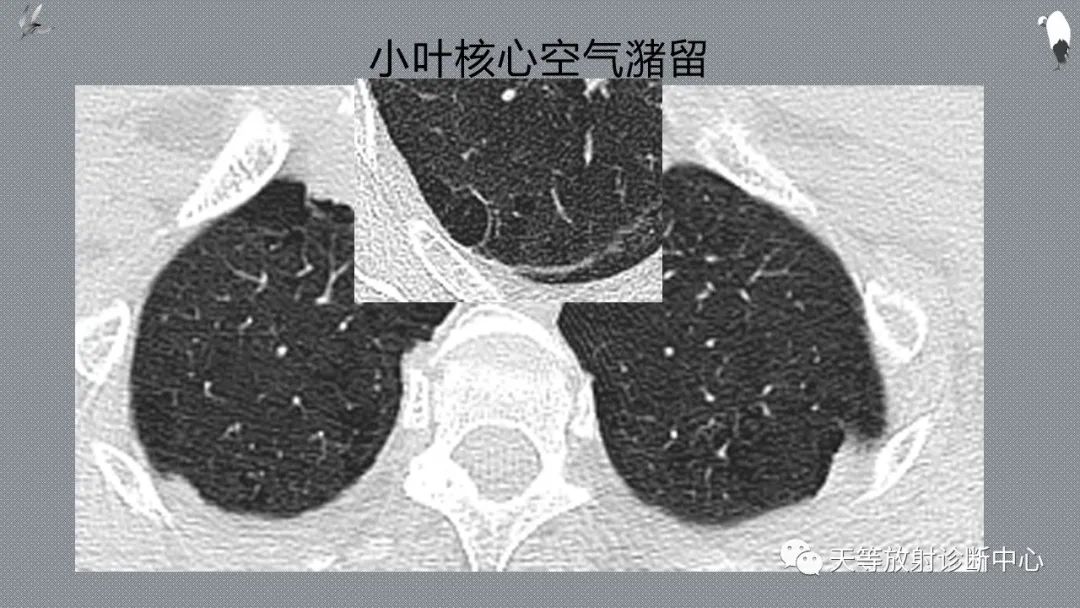

排除肺弥漫性或局限性气道阻塞小气道病变。